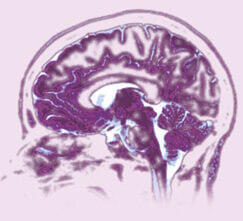

Dans la maladie d'Alzheimer, des doses élevées de vitamine E ralentissent le déclin fonctionnel

alzheimer540 patients (dont 324 femmes) avec une maladie d'Alzheimer probable, âgés en moyenne de 74 ans, ont été enrôlés dans une étude. Tous ont reçu un inhibiteur de la cholinestérase (donépézil, rivastigmine ou galantamine). En plus, 208 d'entre eux ont reçu 700 à 2 000 unités internationales de vitamine E ; 49 d'entre eux avaient un traitement anti-inflammatoire, principalement des médicaments anti-inflammatoires non stéroïdiens, 177 des médicaments anti-inflammatoires et de la vitamine E et 106 ne recevaient ni les uns ni l'autre.

Tous les six mois, les fonctions cognitives des sujets étaient évaluées. Le suivi a duré en moyenne 3,1 années. La supplémentation en vitamine E a eu des effets petits à moyens sur le ralentissement du fonctionnement cognitif. Les médicaments anti-inflammatoires ont eu, eux, un léger effet.